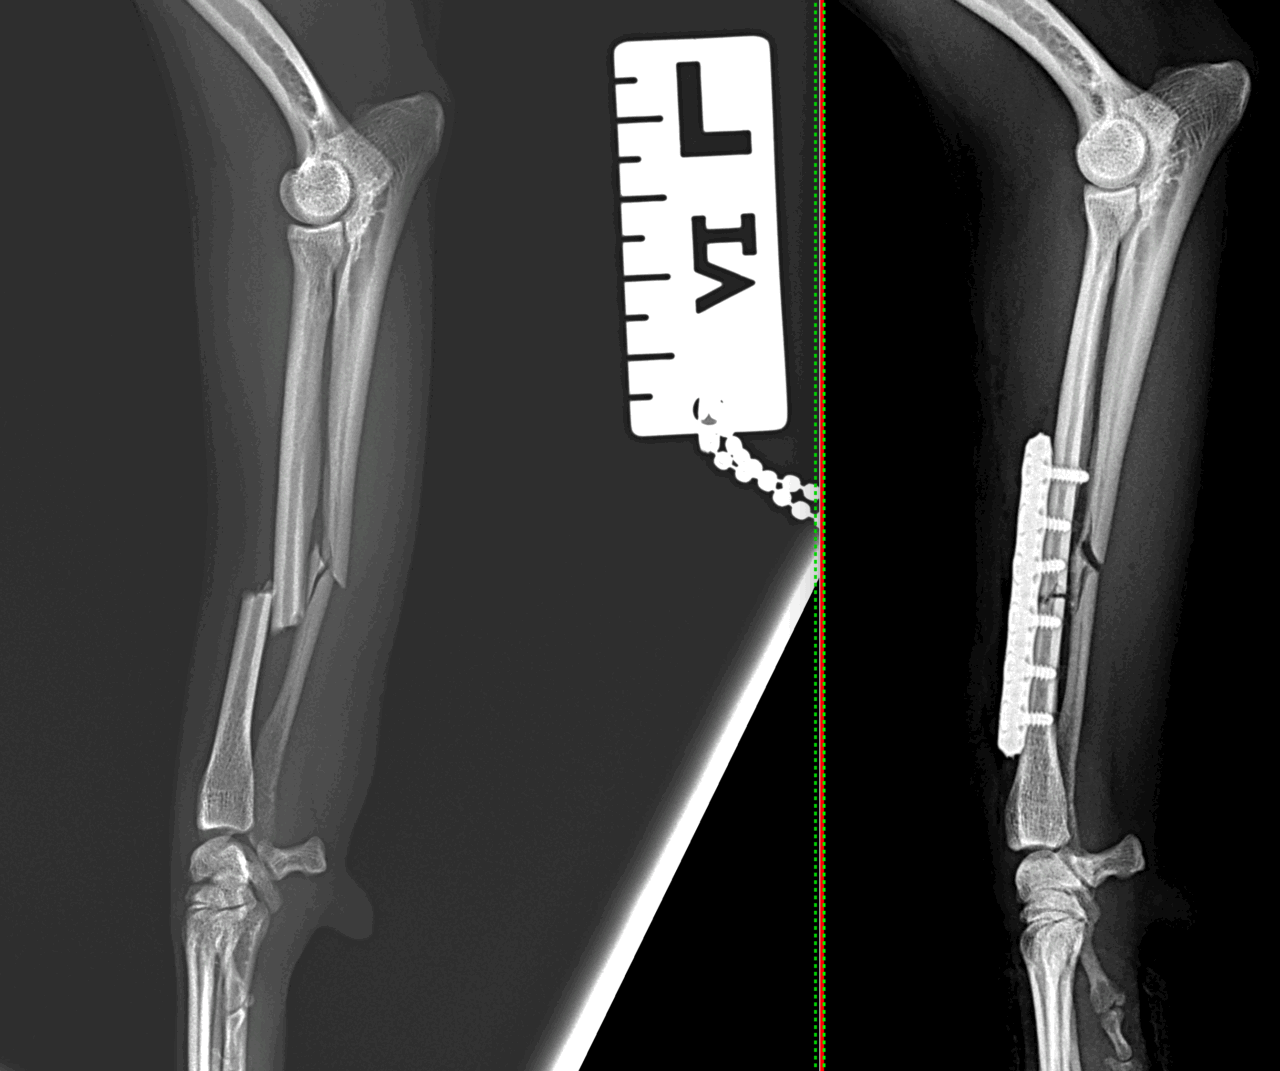

橈骨固定術 #247 小型の柴犬さんの橈骨固定術、かかりつけ医より整復依頼がありました。2.0-Titanium Lock Plateでモノコーテックス整復を行いました。しばらくは安静が必要です。 症例カテゴリー 放射線治療整形外科軟部組織外科脳神経外科内科腫瘍外科救急・集中治療リハビリテーション科腫瘍内科内視鏡科脳神経科呼吸器外科中医・漢方猫の腎移植循環器科